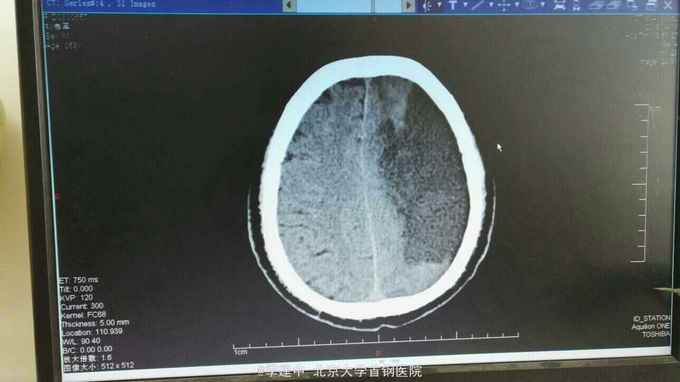

诊断:脑梗死 高血压3级 极高危 2型糖尿病 高脂血症 治疗:入院后给予抗血小板聚集、改善脑供血、清除自由基、扩容,脱水及对症支持治疗。2016.4.16接班后查房发现患者呼之无应答。查体:T:37.7℃;P:95次/分;R:20次/分;BP:202/90mmHg。 深度嗜睡至浅昏迷,呼吸节律尚规整,查体不合作。双侧眼球居中,双侧瞳孔不等大,左侧直径3.0mm,右侧直径约1mm。右侧鼻唇沟浅。双侧Babinski'sign、双侧Chaddock'sign(+)。右侧肢体无自主活动。双肺未闻及干湿啰音,心率95次/分,律齐,双下肢无浮肿。急诊复查头CT示:多发脑梗死,左侧额颞顶叶大面积梗死,建议MRI检查进一步明确。阅片可见侧脑室受压明显,中线移位,有脑疝形成。请神经外科急会诊,建议行去骨瓣减压术。告知患者家属上述情况,家属同意转神经外科行急诊去骨瓣减压术。

患者脑梗塞面积大,水肿难以控制